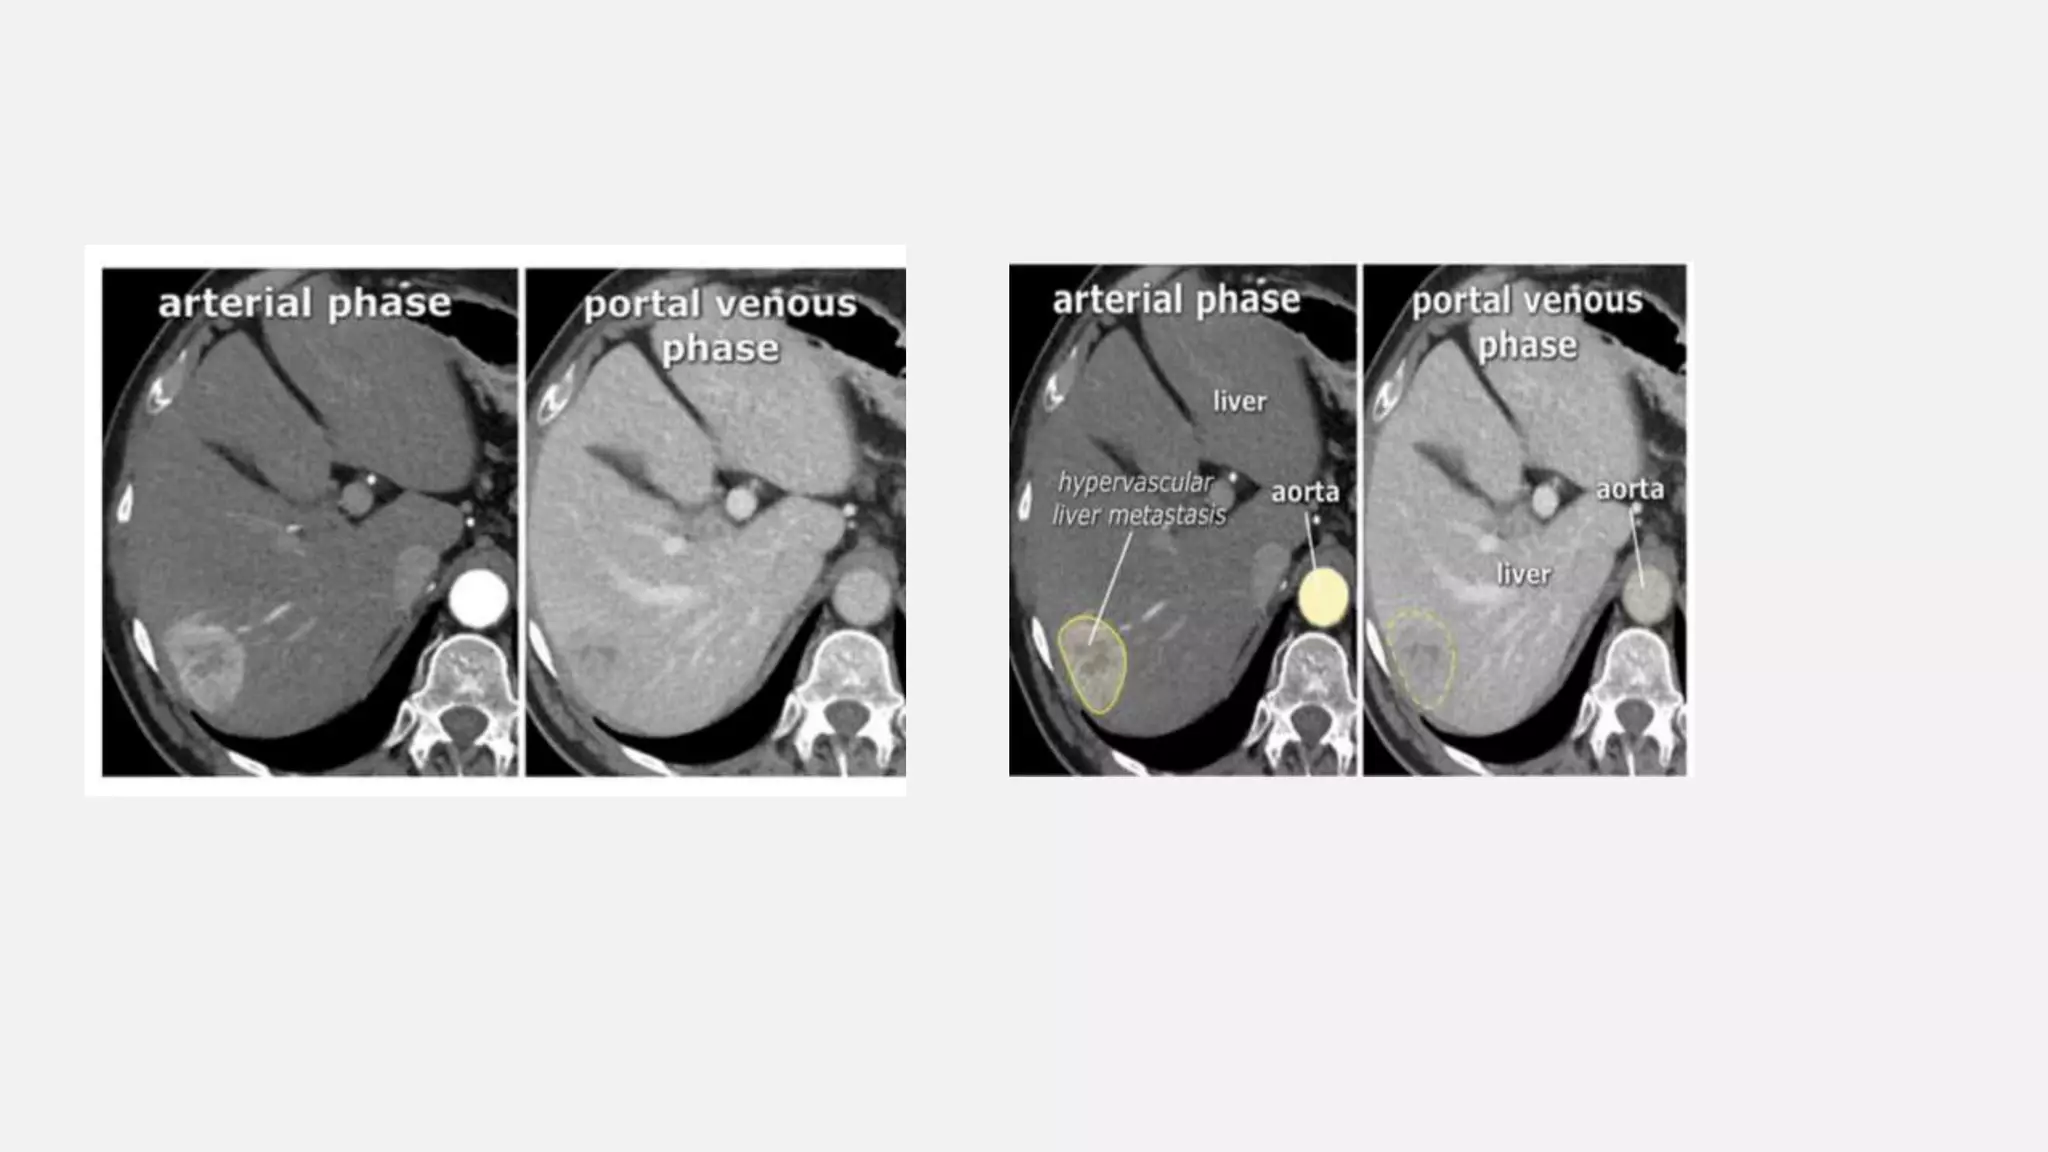

LIVER • All livertumours however get 100% of their blood supply from the hepatic artery. So a hyper vascular tumor will be best seen in the late arterial phase. • A hypo-vascular liver tumor however will enhance poorly in the late arterial phase, because it is hypo- vascular and the surrounding liver does also enhance poorly in that phase. This tumor is best seen when the surrounding tissue enhances, i.e. in the late portal (or hepatic) phase at 75-80 sec p.i. • The

• #37 The conspicuity of a liver lesion depends on the attenuation difference between the lesion and the normal liver. On a non enhanced CT-scan (NECT) liver tumors are not visible, because the inherent contrast between tumor tissue and the surrounding liver parenchyma is too low. When we give i.v. contrast, it is important to understand, that there is a dual blood supply to the liver. Normal parenchyma is supplied for 80% by the portal vein and only for 20% by the hepatic artery, so the normal parenchyma will enhance maximally in the hepatic phase at 70-80 sec p.i. and only a little bit in the late arterial phase at 35-40 sec p.i..

• #38 In the late arterial phase at 35 sec hypervascular lesions like HCC, FNH, adenoma and hemangioma wil enhance optimally, while the normal parenchyma shows only minimal enhancement. Hypovascular lesions like metastases, cysts and abscesses will not enhance and are best seen in the hepatic phase at 70 sec p.i. Fibrotic lesions like cholangiocarcinoma and fibrotic metastases hold the contrast much longer than normal parenchyma. They are best seen in the delayed phase at 600 sec p.i. This late enhancement is comparable to what is seen in cardiac infarcts in MRI of the heart.

• #40 Hypervascular liver metastasis in a patient with a history of renal cell carcinoma. Note it is difficult to see the metastasis in the portal venous phase.